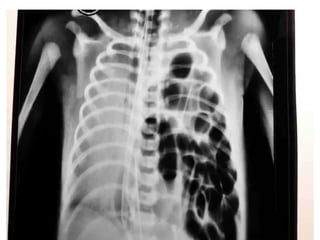

PLAIN X-RAY CHEST & ABDOMEN

• Pneumotharax, Haemothorax

• Free air under diaphragm

• Nasogastric tube, bowel loops

in the chest

• Elevation of the both /Single diaphragm

• Lower Ribs # -Liver /Spleen Injury

• Ground Glass Appearance – Massive Hemoperitoneum

• Obliteration of Psoas Shadow –Retroperitoneal

Bleeding

• #vertebra